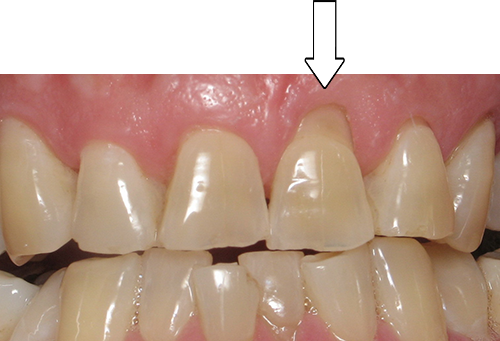

Smile Gallery

Orthodontic Treatment X-ray - After